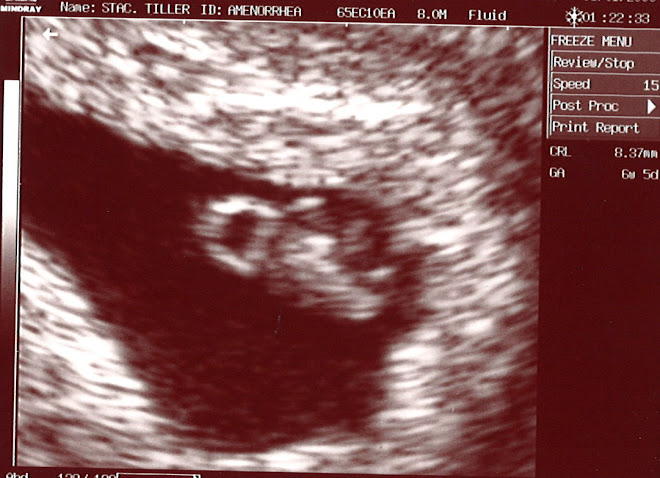

Hello everybody, It's a GIRL and she is ADORABLE! Her name is Harley Grace Tiller and she already has me wrapped around that little finger. I get goosebumps every time I see her move. I am SO excited. I know I said the last pic was my favorite but this is by far my favorite. This was the day we found out she is a girl and she is sucking her thumb. I have included a video and if you watch closely at the end you can clearly see her sucking her thumb. Stacey is so awesome. She is finally getting over the nausea and more beautiful everyday. The belly grows a little every night (some nights more than others lol). We have began shopping for baby items and I had forgotten how fun this is. WOW, things have really changed in the last 20 years. When Casey was a baby we had a basic car seat with like a rope you had to tie in a knot to hold her in. Now they have all these complicated hooks, clasps, locks, combinations and mind boggling instructions. I guess I'll have to figure it out. Thank you to everyone for your thoughts, prayers and kind words. Please continue to keep us and little Harley in your prayers. Stacey is registered at Babies R'Us, Target and BeyondBedding.com.